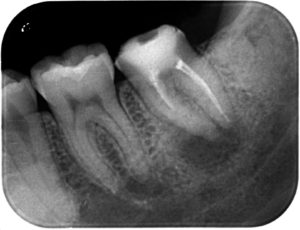

レントゲン撮影を行ったところ、

下の青丸の個所が黒くなっているのがわかるでしょうか??

この歯は以前、神経を取り除き、空洞になった神経の部屋に白い薬を詰めて、蓋がしてある歯でした。

しかし経年的に中に入っているお薬が劣化し、溶け出てしまった結果、中で感染を起こし根っこの先に膿が溜まってしまっています。